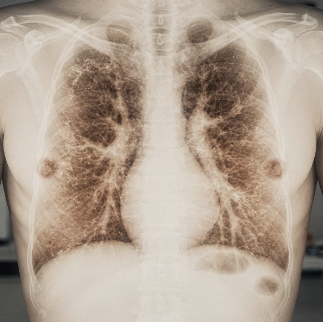

2주 이상 지속되는 가래, 피 섞인 가래, 체중 감소, 숨이 차고 가슴이 조이는 증상은 단순한 가래가 생기는 원인 이상을 시사하므로 반드시 진료가 필요하다. 고열, 누런 또는 악취 나는 가래, 흉통이 동반될 경우 폐렴, 농양, 폐암 등 중증 질환이 가래가 생기는 원인일 수 있어 흉부 X선, 폐 기능검사 등 정밀 검사가 권장된다.

특히 흡연자와 고령자라면 이런 가래가 생기는 원인을 절대 방치해서는 안 된다.